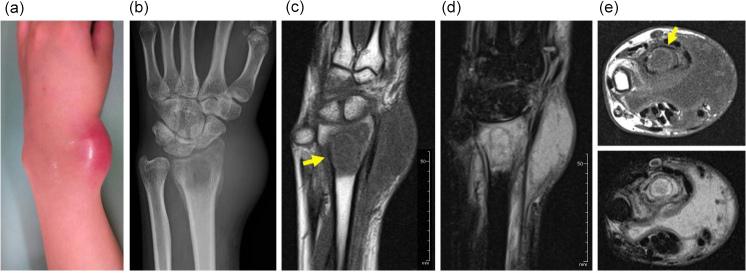

Although characteristic, is a rare cause of osteomyelitis, especially in healthy individuals. A 25-year old primigravida at 29 weeks' gestation noticed pain and swelling in her right wrist. Her leukocyte count was normal, but her C-reactive protein level was slightly elevated, at 1.1 mg dL (normal range, mg dL ). Plain radiography showed an osteolytic lesion in the distal radius, and magnetic resonance imaging (MRI) showed an extraosseous fluid collection with bone edema in addition to the osseous lesion. After a needle biopsy was performed, the skin overlying the lesion became ulcerated at the site of the needle tract. We drained whitish pus from the site; both this pus and the original biopsy specimen grew on culture. We diagnosed osteomyelitis and began intravenous antibiotic therapy, avoiding oral quinolones to prevent fetotoxicity. Her symptoms resolved, as did the bone edema and fluid collection. Ossification occurred at the site of osteolysis, with localized abnormal signal intensity persisting on MRI. This rare case of osteomyelitis was treated without surgery; the patient's pregnancy influenced the treatment course.